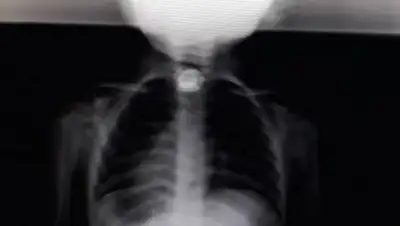

Из дыхательных путей девочки врачи извлекли 10-тенговую монету.

Двухгодовалую девочку с жалобами на затрудненное дыхание в приемный покой Бейнеуской ЦРБ доставили вчера, 18 марта. Сделав рентген, медики обнаружили в дыхательных путях ребенка инородный предмет, передает Zakon.kz со ссылкой на ИнАктау.

"Врачи приняли решение вытаскивать инородный предмет, используя опыт испанских врачей, который, по словам директора Бейнеуского ЦРБ, он получал у заграничных коллег. Из дыхательных путей девочки врачи извлекли 10-тенговую монету. В настоящее время здоровью маленькой пациентки ничего не угрожает", - рассказали в пресс-службе облздрава.